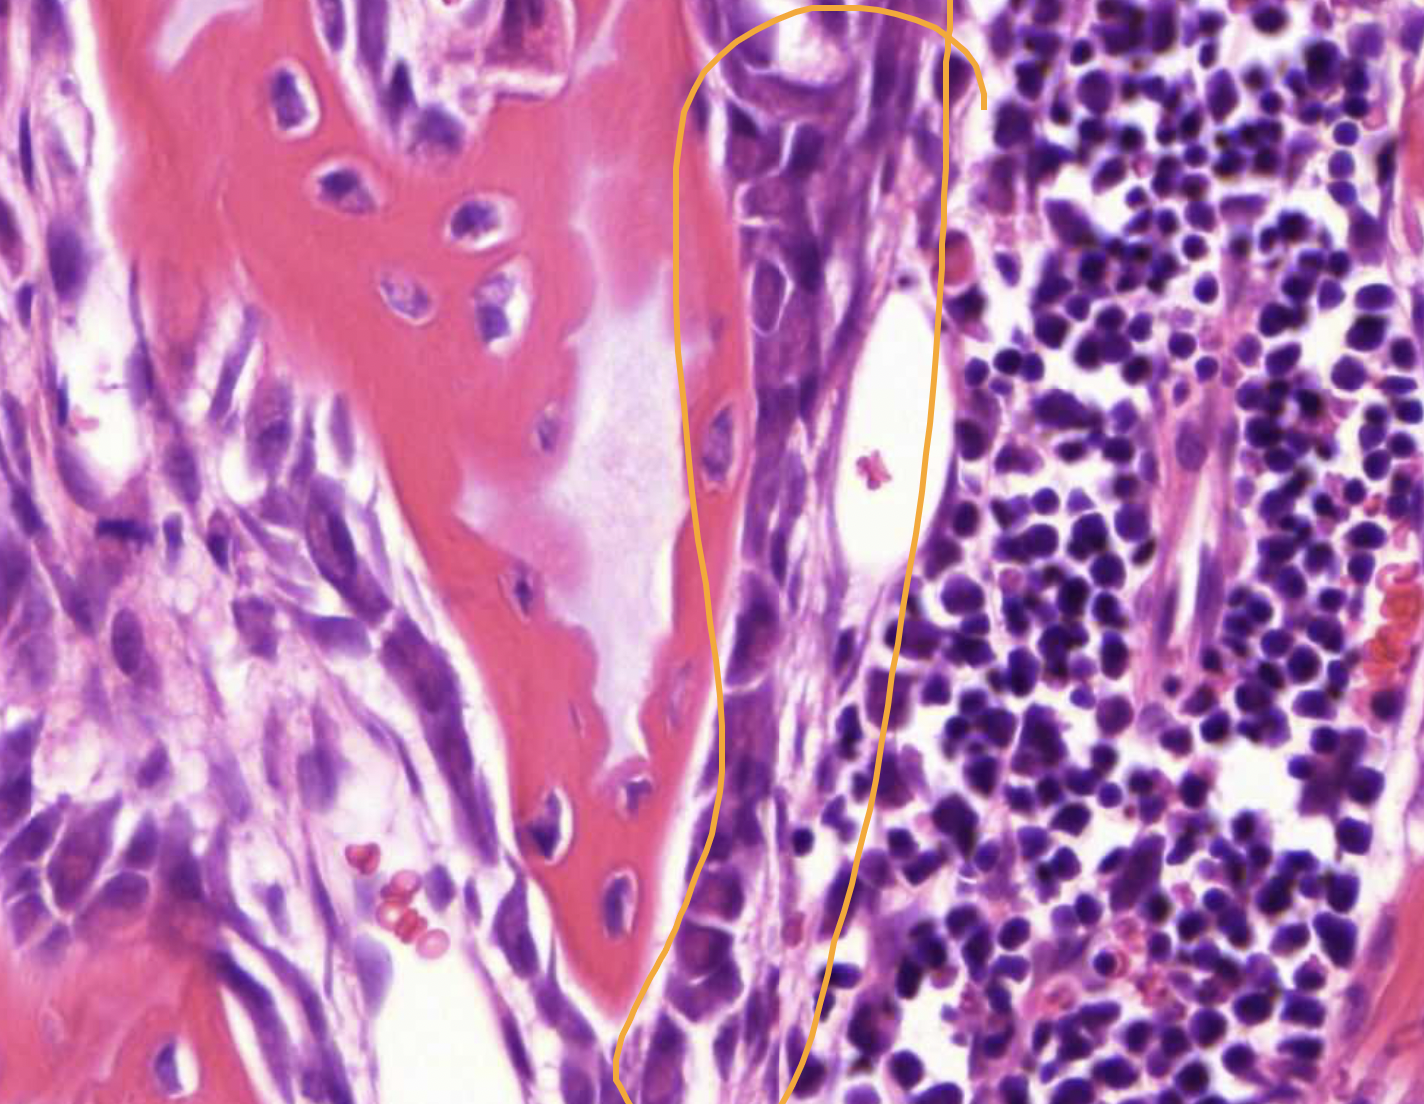

term image

• endosteum - inside or cortical bone

• peristeum - outside or cortical bone